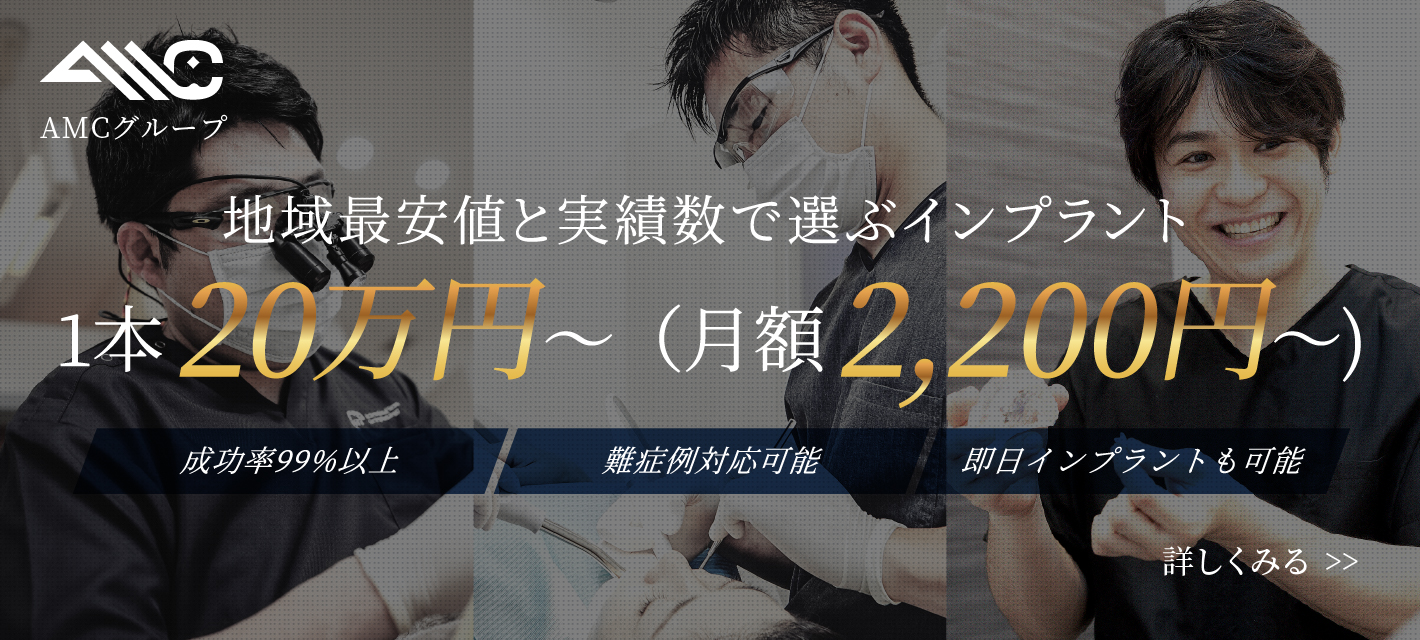

インプラント

インプラント治療について

インプラント治療とは

インプラント治療とは、歯を失った箇所に人工の歯根(インプラント)を埋入し、歯を補う治療法です。

当院のインプラント治療は、お口全体のバランスを考慮して行います。CT画像で精密に診査・診断を行い、かみ合わせのバランスを綿密にシミュレーションします。顎骨の幅や高さには個人差があり、状態によって、そのままではインプラントの埋入が難しい場合もあります。そのような場合には外科手術で骨量を増やしてからインプラントの埋入を行うので、骨の量が不足している方でも手術が可能です。